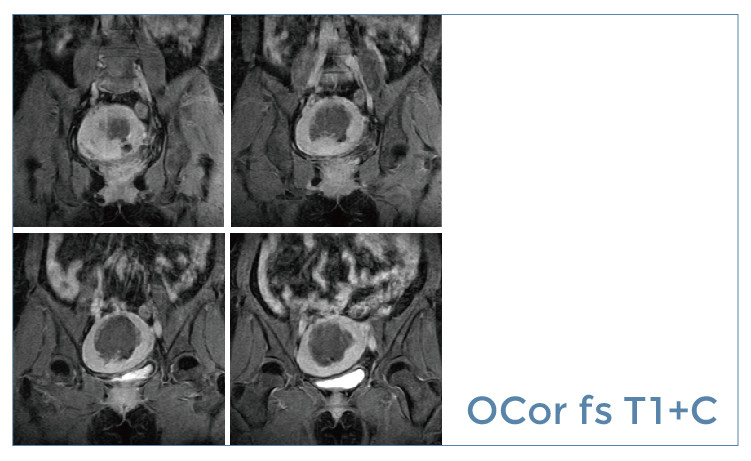

【朗润影像档案】磁共振影像病例分享(编号20190621)